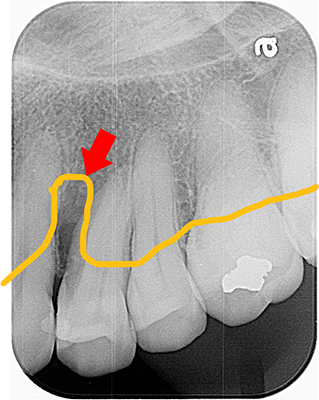

当院での歯周組織再生療法の治療例

当院でリグロス治療を行い、約8か月後には骨の再生が確認できます。

レントゲン上で重度骨吸収が認められます

- 歯茎が出血・腫れ・痛み・膿が出ていて、歯周ポケット12mmありました。

- ブルーラジカルにて歯周病菌の殺菌を行いました。

- 2週間後には上記症状が消失し、歯周ポケットも4mmとなり歯茎も引き締まって健康な状態となりました。

- 13,000円 (1本)

- 1回